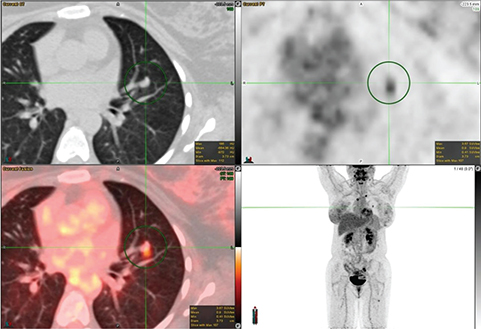

The FDG avidity of lung cancer is mainly dependent on two factors: tumor size, and histology. For nodules greater than 8 mm, 18F-FDG PET/CT has a high negative predictive value in excluding malignancy (20). Squamous cell carcinoma tends to have a higher uptake as shown in Figure 3. Low-grade adenocarcinoma, mucinous adenocarcinoma, colloid carcinoma, and typical carcinoid can have very low FDG avidity. Bronchoalveolar carcinoma (BAC), a well-differentiated subtype tends to have peak SUV (1.5 ± 0.2) lower than all other non-BAC adenocarcinomas (SUV, 3 ±1.5). False positive FDG uptake can be seen in infectious and inflammatory lesions.

Fig 3

Figure 3. Right upper lung mass that was pathologically confirmed as squamous cell carcinoma. FDG PET/CT images include axial CT (top left panel), axial PET (top right panel), fused axial PET/CT (bottom left panel), and maximum intensity projection (MIP) PET image (bottom right panel). In the green circle, there is a lobulated and spiculated right upper lobe mass on CT with intense FDG uptake on PET.

Accurate staging of lung cancer is mandatory after the diagnosis for appropriate patient management. Many guidelines such as the National Comprehensive Cancer Network (NCCN), the ESMO Clinical Practice Guidelines, the American College of Radiology Appropriateness Criteria, the guidelines of the Society of Nuclear Medicine and Molecular Imaging, and the guidelines of the American College of Chest Physicians recommend 18F-FDG PET/CT for evaluation of patients with stage I to stage IV NSCLC (2124). For the staging of NSCLC, the most standardized and recognized system is the TNM system, where T denotes the size of the primary tumor, its location and level of invasion; N indicates the status of regional lymph nodes; and M refers to the presence or absence of more distal metastases (25). FDG PET/CT plays a vital role in the staging of T, N, and M of lung cancer and an example of FDG avid primary and metastatic tumors is shown in Figure 4.

Fig 4

Figure 4. Right upper lobe lung mass that was pathologically confirmed as poorly differentiated non-small cell lung cancer. FDG PET/CT images include axial CT (top left panel), axial PET (top right panel), fused axial PET/CT (bottom left panel), and maximum intensity projection (MIP) PET image (bottom right panel). In the green circle, there is a spiculated pleural based right upper lobe mass with surrounding interlobular septal thickening on CT with intense FDG uptake on PET. There are additional FDG-avid metastatic foci within the lungs and mediastinal lymph nodes.